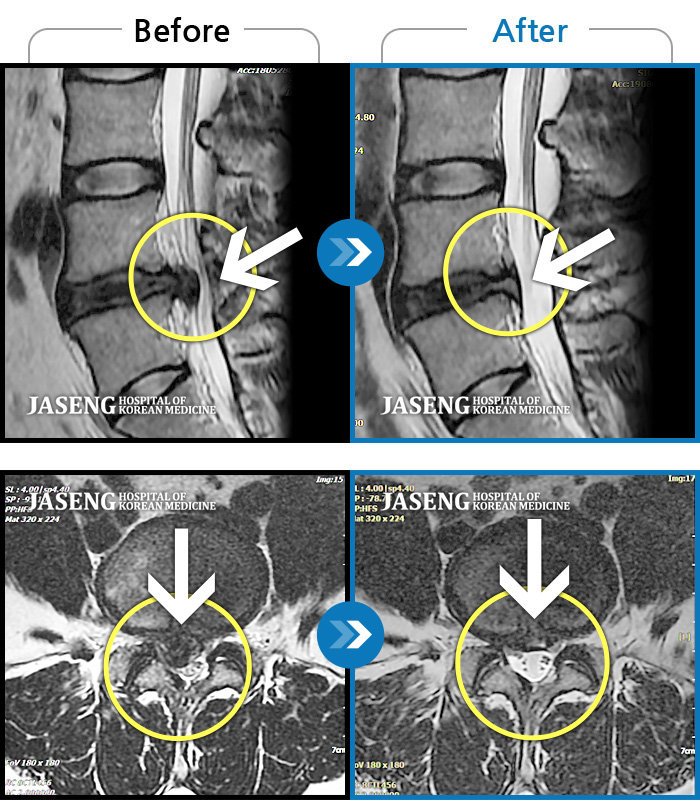

MRI 치료사례

우측 허리 및 골반 통증, 우측 다리에 통증과 저림